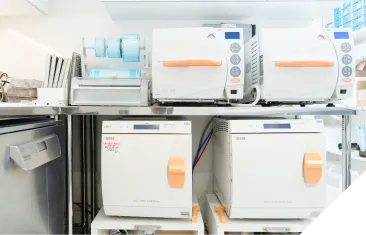

手術は必ず専用の個室オペ室にて行います。大学病院の手術室レベルに準じた徹底した衛生管理に努め、器具は世界最高水準の「クラスB」滅菌器で完全に滅菌し、術者はもちろん、お部屋全体を清潔な状態に保って手術に臨みます。また、術後も適切な抗生剤の処方と消毒で、感染リスクを最小限に抑えます。